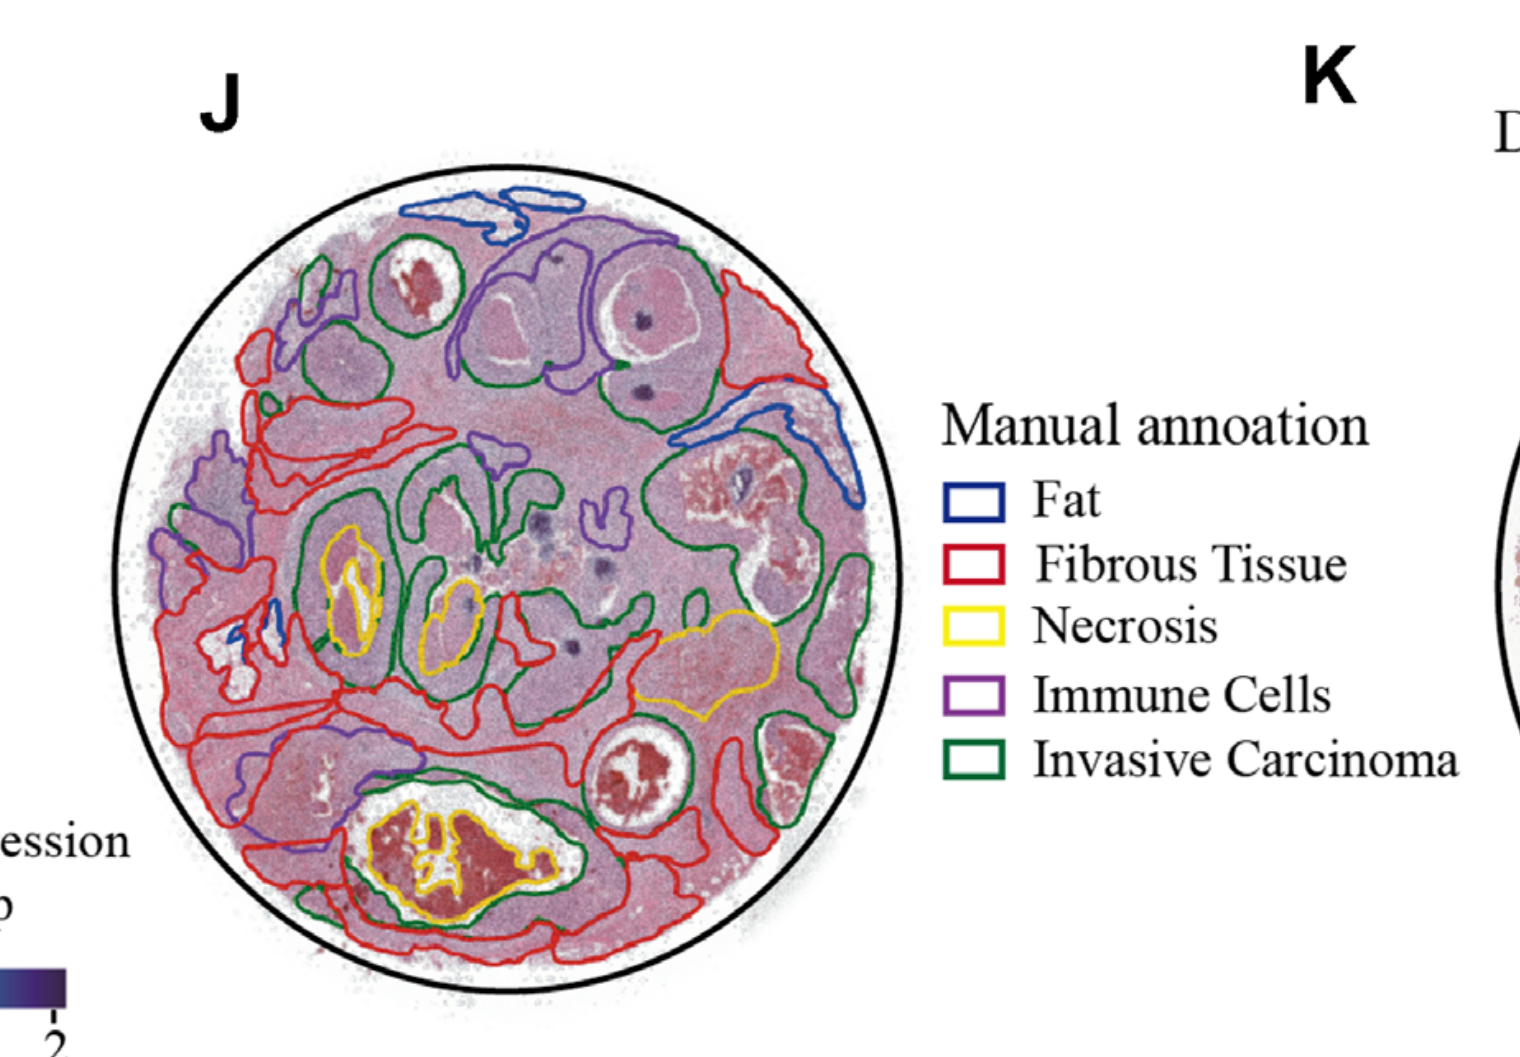

Wei R. et al. - 2022

Spatial charting of single-cell transcriptomes in tissues

Condition Dimension

N/A

Data Components

Biological Annotation

Data

Metadata

None

Modality

Sequencing-based

Resolution of observation

Functional tissue unit

Visualized Elements

Observation

Biological

Tissue

Abstraction

None

Chart Type

Histological image

Communicative/Contextualization

Annotation

Comparative Design

None

Layout

Spatial : Physical

Scalability Strategy

None (Item-level)

Where are tumor regions located within the spatial architecture of a tissue section?